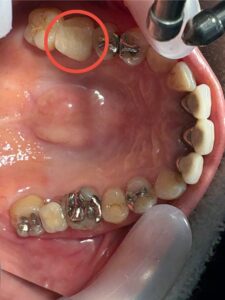

口腔内の写真

骨造成により十分な骨量が確保でき、

インプラントも安定して埋入できました。

術後の経過も良好で、「自分の歯のようにしっかり噛める」と大変満足していただけました。